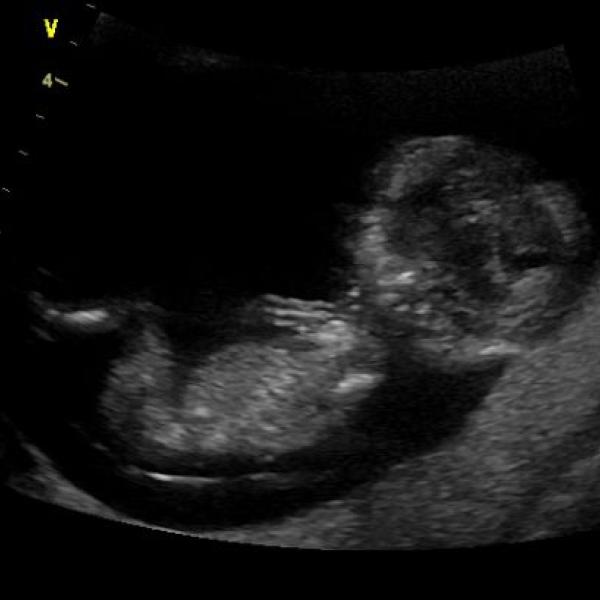

Holky, tak se připojuji a posílám vám na ukázku také můj pupík.

Ahoj holky, tak se jdu s vámi také podělit o můj včerejší screening. Vše je naštěstí v naprostém pořádku, takže jsem mooooc šťastnáá!!